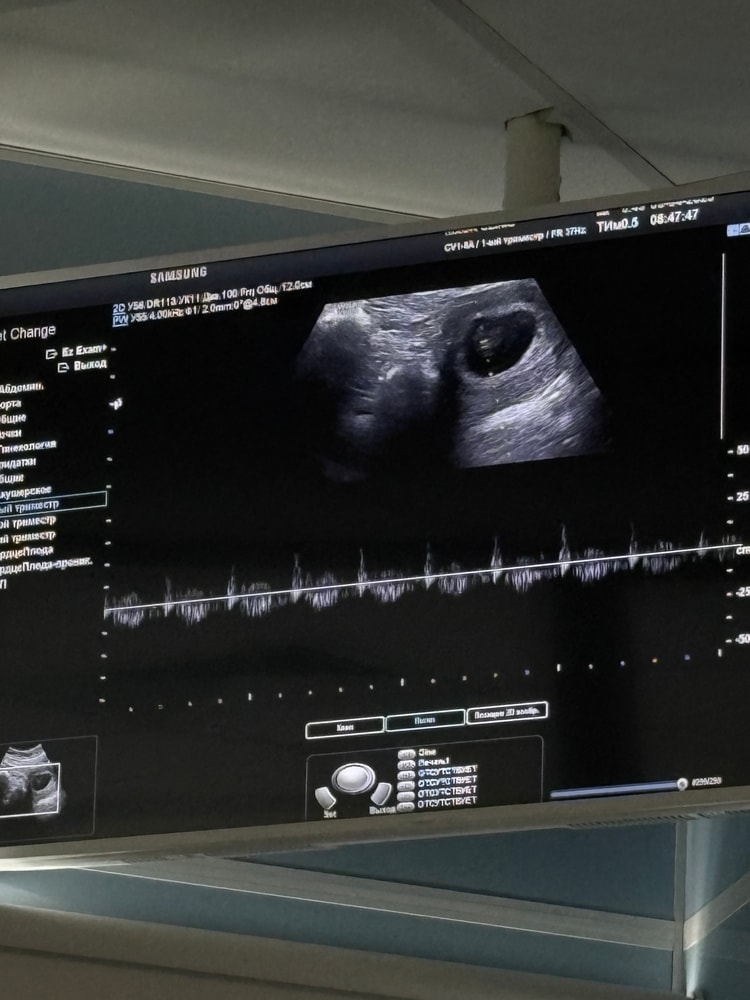

30дпп. УЗИ 💙

сегодня я впервые услышала сердечко нашего малыша! 7нед1день, КТР 8.5, ЧСС 152 😍

еще 10 дней назад его даже не было на узи, а сегодня он уже такой большой и с таким активным сердечком 🥹расти, наш мальчик!